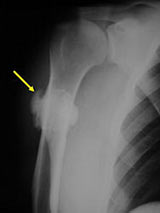

- Proximal humerus (15%); Tibia (10%); Fibula (3%), Radius, Ulna

X-Rays:

- Lobulated and ossified exophytic mass (cauliflower-like) adjacent to the cortex; attached to metaphyseal cortex via a broad base

- Centrally, the tumor is radiodense (demonstrates ossification)

- Peripherally there may be small radiolucies that represent low grade cartilaginous lobules, fibrous tissue or fat

- The underlying cortex may be thickened

- There is no periosteal reaction since the tumor comes from the outer layer of the periosteum and therefore does not elevate the periosteum.